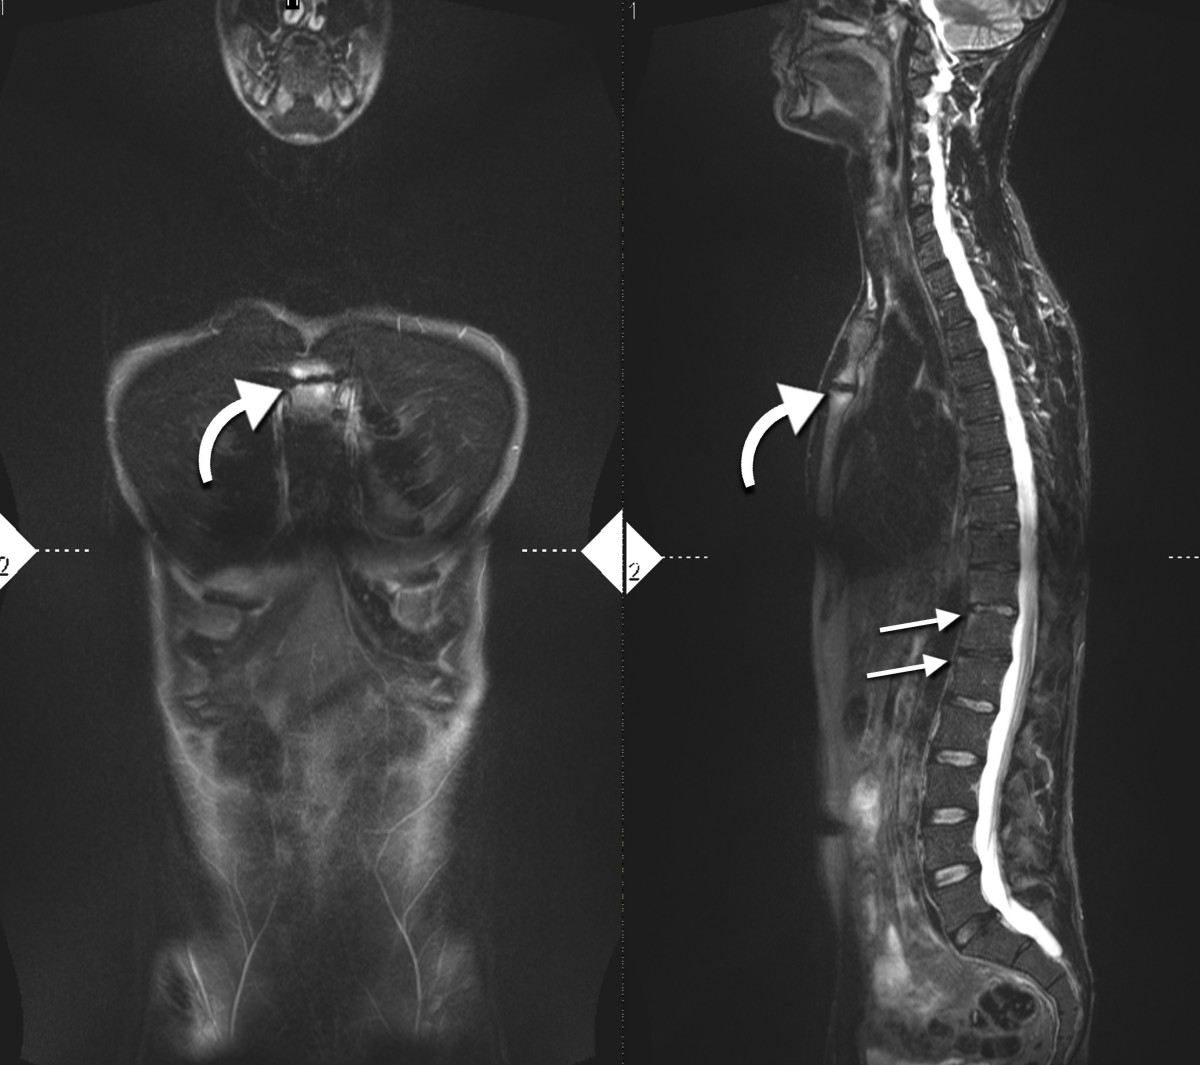

이러한 기준만으로 진단이 어려운 경우 자기 공명 영상(MRI)이 유용할 수 있다.[20][22] MRI는 천장관절염의 천장관절 염증을 보여줄 수 있다.

4. 1. 영상 검사

단순 X-ray에서 가장 초기에 나타나는 변화는 천장관절의 침식과 경화이다.[23] 침식이 진행되면 관절 공간이 넓어지고 뼈가 경화된다. X-ray 척추 사진은 신데스모파이트라고 하는 뼈 가시 형성으로 척추가 사각형이 되는 것을 보여줄 수 있으며, 이는 대나무 척추 모양을 유발한다. X-ray 진단의 단점은 강직성 척추염의 징후와 증상이 일반적으로 단순 X-ray에서 확인 가능한 변화가 나타나기 7~10년 전에 이미 나타난다는 것이다. 이는 적절한 치료법을 도입하기 전에 최대 10년의 지연이 발생할 수 있음을 의미한다.[23]

보다 빠른 진단을 위한 옵션으로는 천장관절의 CT 촬영과 MRI가 있지만, 이러한 검사의 신뢰성은 아직 불분명하다.